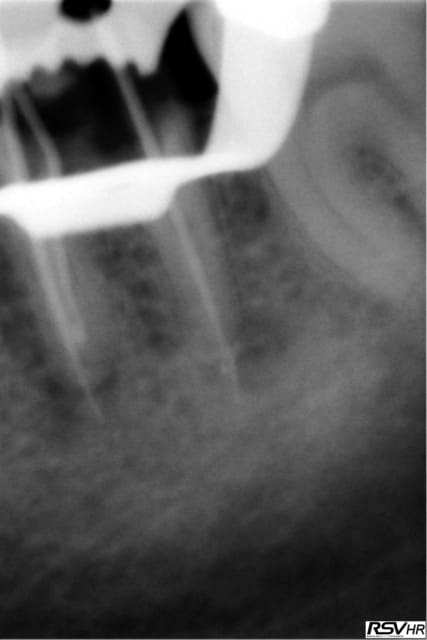

UN exemple de RTE

dépose inlay+couronne en 2009

retraitement sous digue indispensable(même sur dents antérieures la digue ce n'est pas pour faire jolie,c'est pour permettre à l'hypochlorite de rester à demeure tout le long du retraitement;il faut que çà "baigne" pour avoir une chance de

guérison apicale)

ici traitement sous hypo+digue +r-endo;il y a un dépassement léger au périapex

en 2015 guérison apparente du périapex(1h30 de retraitement!)

la dépose de l'inlay avec des ultrasons;désobturation acétate éythyle r-endo gutta compactage mac spadden

5eme photos en2009 et 2010;la dernière en 2015